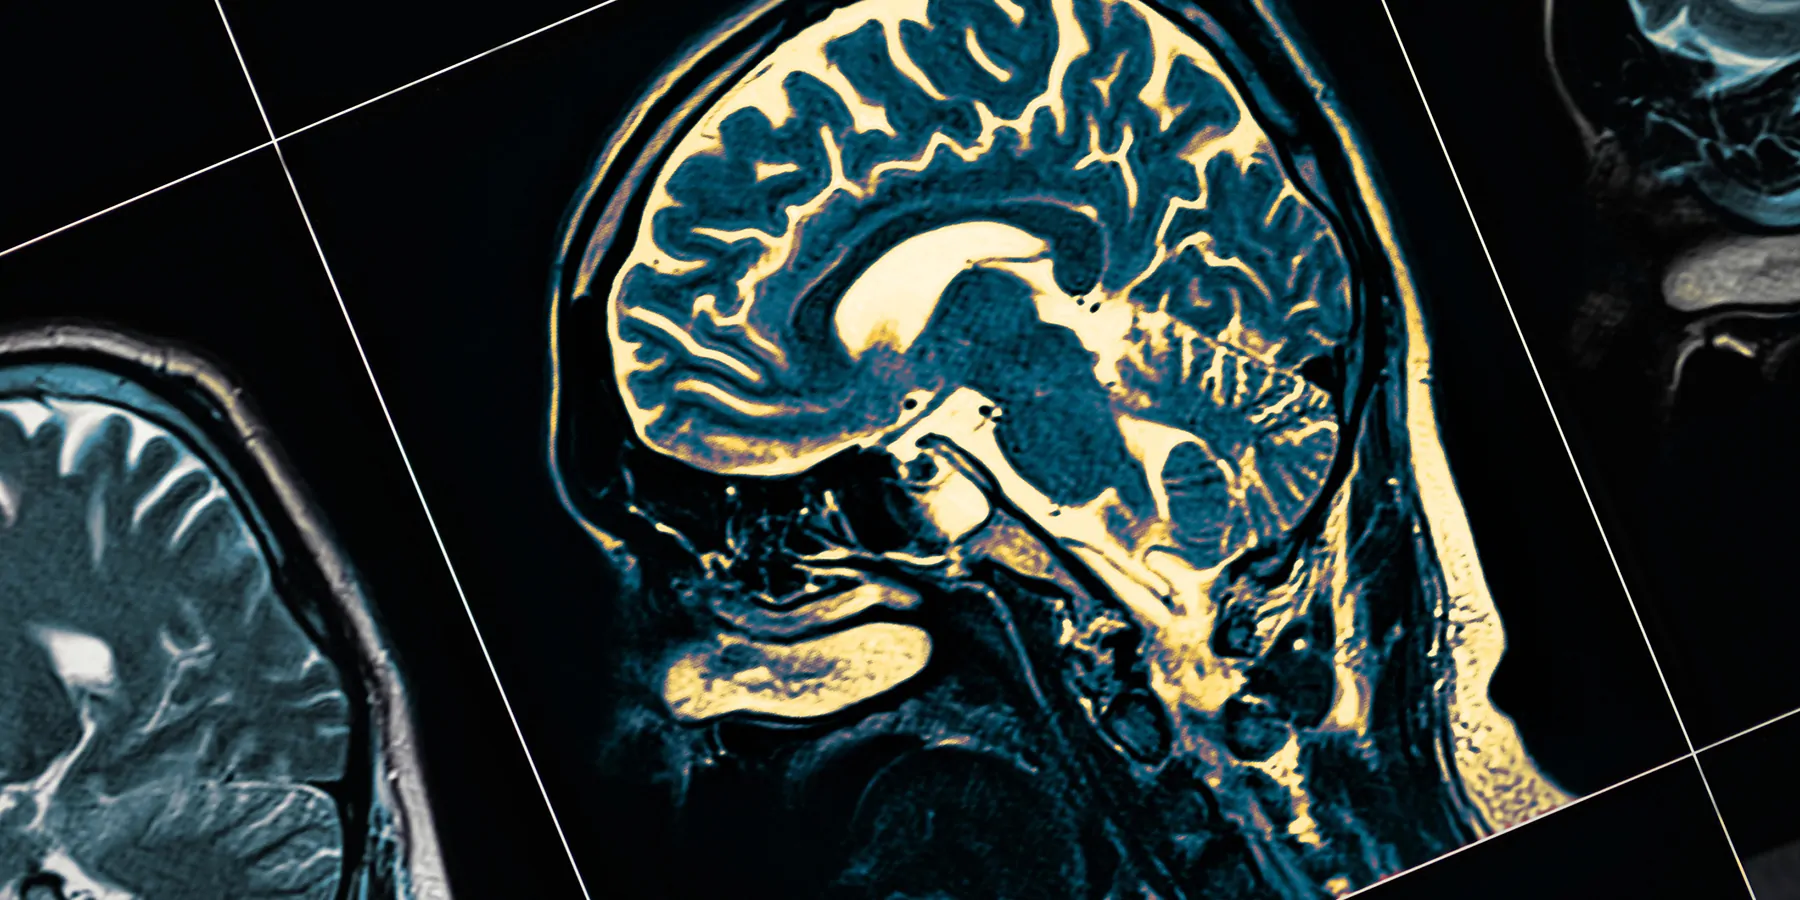

Florbetapir (18F) positron electron tomography and magnetic resonance imaging were also performed. A combination of the APOE genotype with plasma p-tau and serum GFAP demonstrated exceptional performance in distinguishing Aβ status. Furthermore, baseline GFAP levels exhibited a strong association with cognitive decline over time and brain atrophy—with higher GFAP levels predicting a faster rate of neurodegeneration.